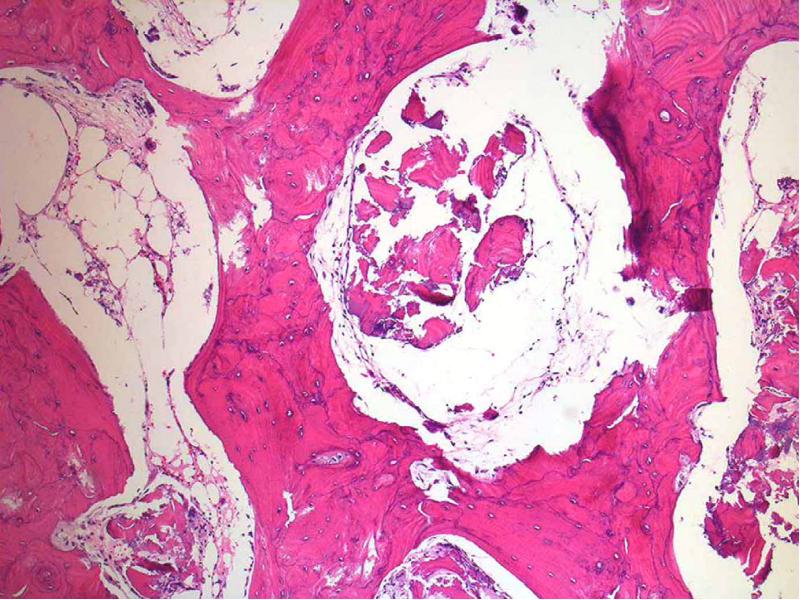

- 14. Микроскопическая картина Гистологически напоминает эмалевый орган Кистозная Фолликулярная Плексиформная Акантоматозная Базально-клеточная